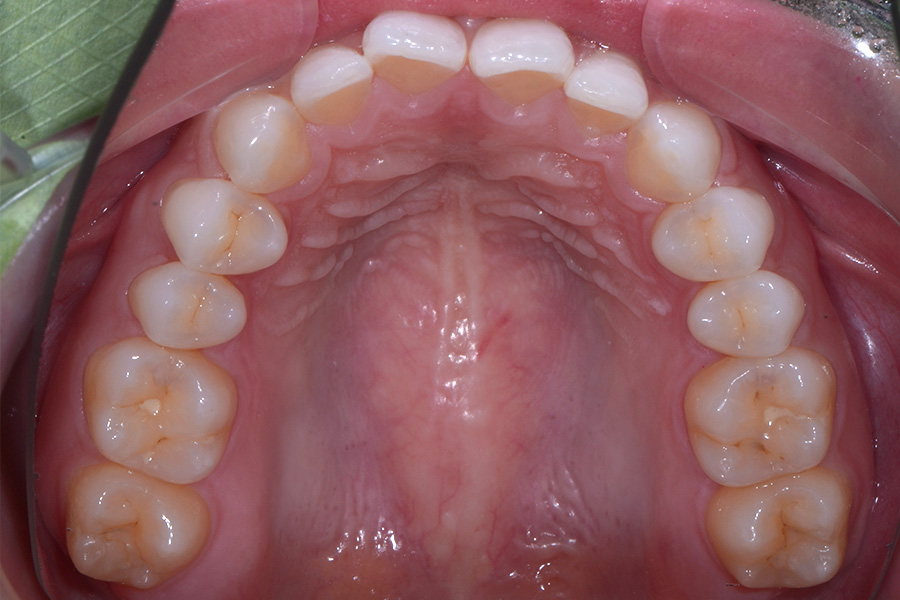

治療前

治療後

主訴 前歯のすきっ歯と捻じれを治したい

治療内容 上下顎ラビアル矯正(表側矯正)